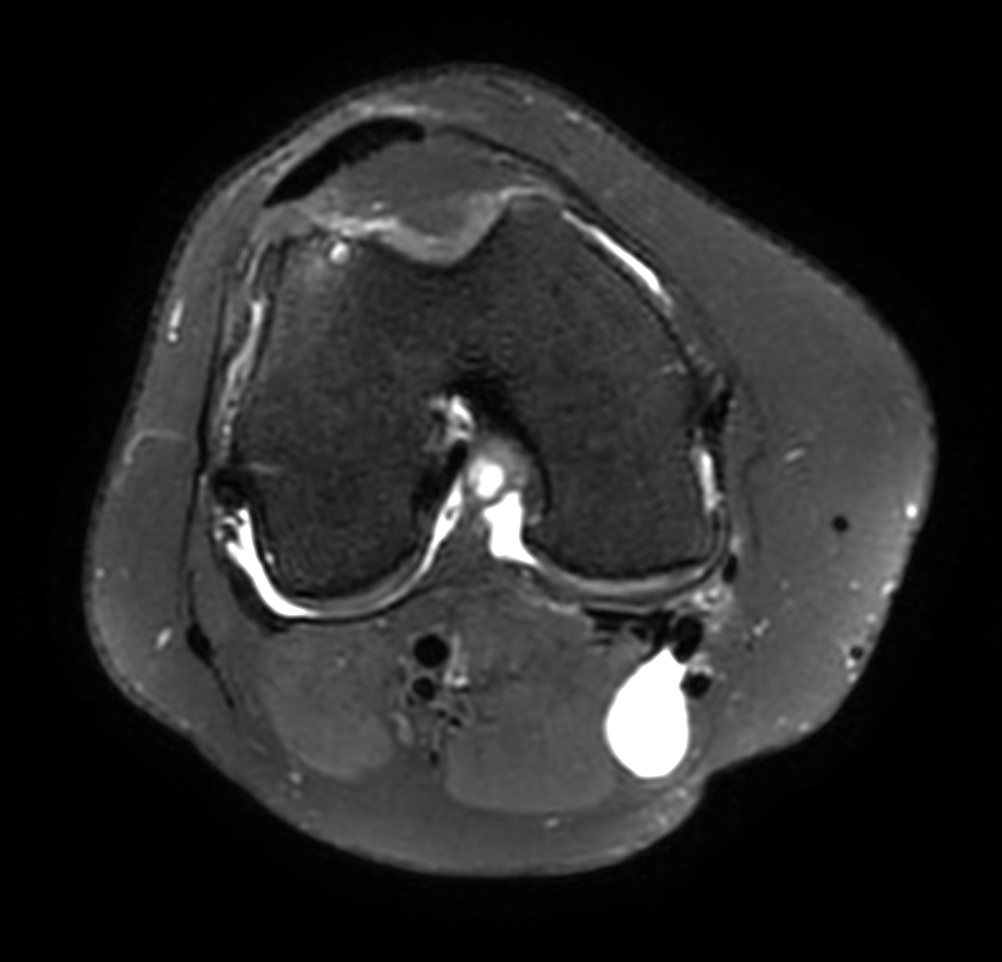

Axial T2w calc (source)